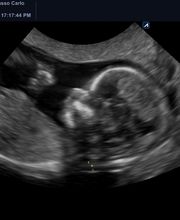

OstetriciaGalleria